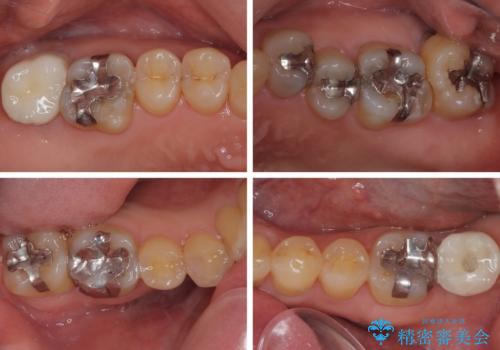

外側に飛び出している歯 部分矯正を用いた奥歯の補綴治療

上顎左右の歯をアンカースクリューを用いた部分矯正により位置を修正し、オールセラミッククラウンにて補綴治療を行うこととしました。

矯正治療に時間はかかりましたが、外側に飛び出した歯が内側に収まったことで、非常に歯が磨きやすくなったとのことでした。